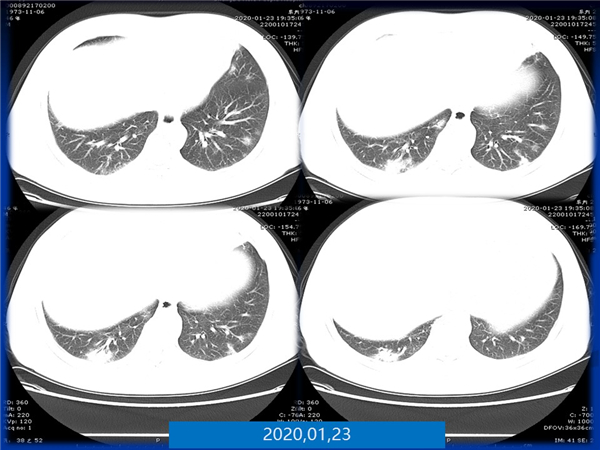

【病例分享】新型冠狀病毒感染肺部CT影像4例(常德市第一人民醫(yī)院)